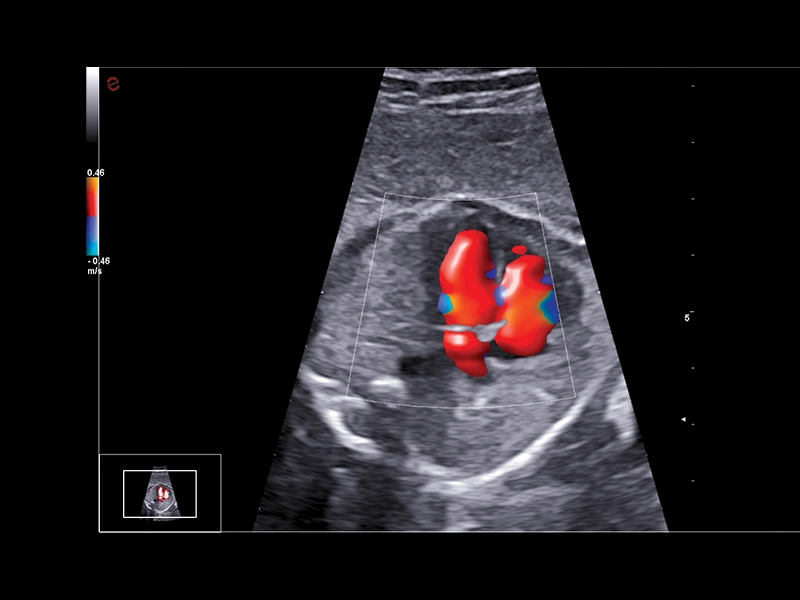

MyLab™9 Platform - Ultra-sensitivity Colour Doppler for precise visualization pulmonary veins

MyLab™9 Platform - Ultra-sensitivity Colour Doppler for precise visualization pulmonary veins